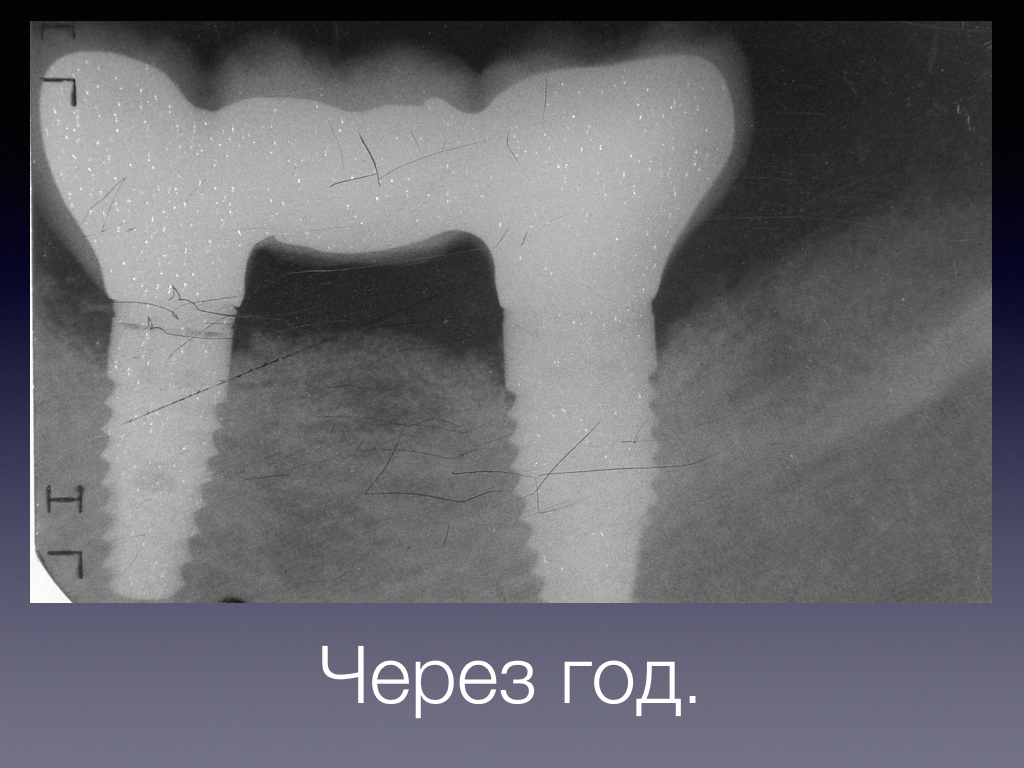

Периимплантит и БИОИМПЛАНТ ГАП -ОБНОВЛЕНО